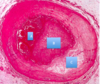

What is B in the lung?

Bronchiole